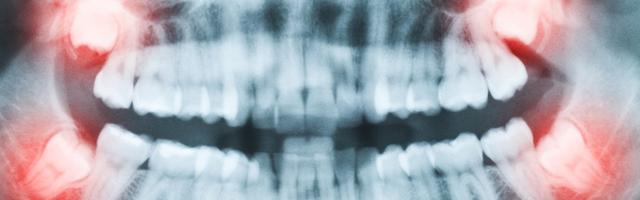

Wisdom teeth are jokingly called the dentists best friend: they almost always need to be removed or have some kind of problem with them. In this article we wish to go about explaining why wisdom tooth pain and wisdom tooth issues are so frequent, and what kind of issues they are. We also wish to describe the different kinds of problems that frequently occur with wisdom teeth, and thus can prepare you for what you may experience.